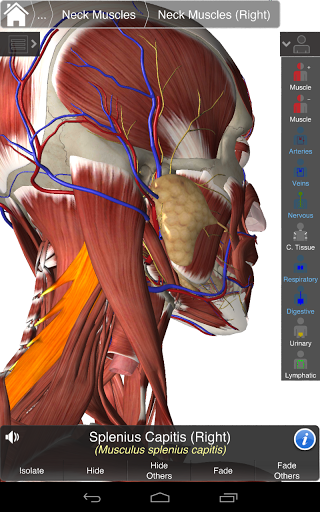

Essential Anatomy 3 represents the latest in groundbreaking 3D technology and innovative design. A cutting edge 3D graphics engine, custom built by 3D4Medical from the ground up, powers a highly-detailed anatomical model and delivers outstanding quality graphics that no other competitor can achieve.

The app represents a unique approach to learning general anatomy. The graphics are unparalleled and make learning, through the use of informative content and innovative features, a rich and engaging experience.

Essential Anatomy 3 is responsive, visually stunning and effortless. The app is fully 3D, meaning that you can view any anatomic structure in isolation, as well as from any angle.

Clever functionality found within the app allows the user to strip away layers of muscle via the ‘scalpel’ tool. This app provides users with the ability to turn on/off systems without the need to deselect individual structures or muddle through a multitude of predefined regional tabs, like other apps.

---- Correct audio pronunciation for every structure

---- Latin nomenclature for each anatomical structure